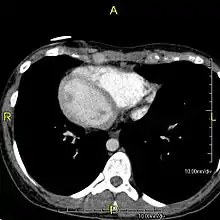

وُجِد الانعكاس الجذعي في حوالي 0.01% من البشر،[2] أو في حوالي شخص من كل 10,000. في الحالة الأكثر شيوعًا، الانعكاس الجذعي كليًا، يكون هناك تبديل كامل لجميع أعضاء البطن. لا يكون القلب في موضعه المعتاد أيسر الصدر ولكن على اليمين، وهي حالة تعرف باسم قلبٌ يمينيّ. ولأن العلاقة بين الأعضاء لا تتغير، فلا يعاني الأشخاص من أي أعراض أو مضاعفات طبية، على الرغم من وجوب تعريف وتحذير الطاقم الطبي في حالات الطوارئ من أن الأعضاء الداخلية للمريض منعكسة عن الوضع الطبيعي، على سبيل المثال للاستماع إلى ضربات القلب على اليمين وليس الجانب الأيسر من الصدر.[3]

التأثير على التشريح

تؤثر الحالة على جميع التراكيب الرئيسية داخل الصدر والبطن. إذ تكون الأعضاء منقولة عبر المستوى السهمي. يقع القلب على الجانب الأيمن من الصدر، والمعدة والطحال على الجانب الأيمن من البطن بينما الكبد والمرارة على الجانب الأيسر. يتواجد الأذين الأيمن الطبيعي في القلب على اليسار، والأذين الأيسر على اليمين. يُعكس تشريح الرئة فيكون للرئة اليسرى ثلاثة فصوص في حين للرئة اليمنى اثنان من الفصوص. تنعكس الأمعاء وغيرها من التراكيب الداخلية والأوعية الدموية والأعصاب واللمفاويات أيضًا.

إذا انعكس القلب إلى الجانب الأيمن من الصدر، فإنه يعرف باسم "الانعكاس الجذعي مع قلب يميني" أو "الانعكاس الجذعي الكُلِّي". إذا بقى القلب على الجانب الأيسر الطبيعي من الصدر، وهي حالة نادرة جدًا (1 من كل 2,000,000 شخص)، فإنه يعرف باسم "الانعكاس الجذعي مع أيسريَّة القلب" أو "الانعكاس الجذعي غير الكُلِّي".